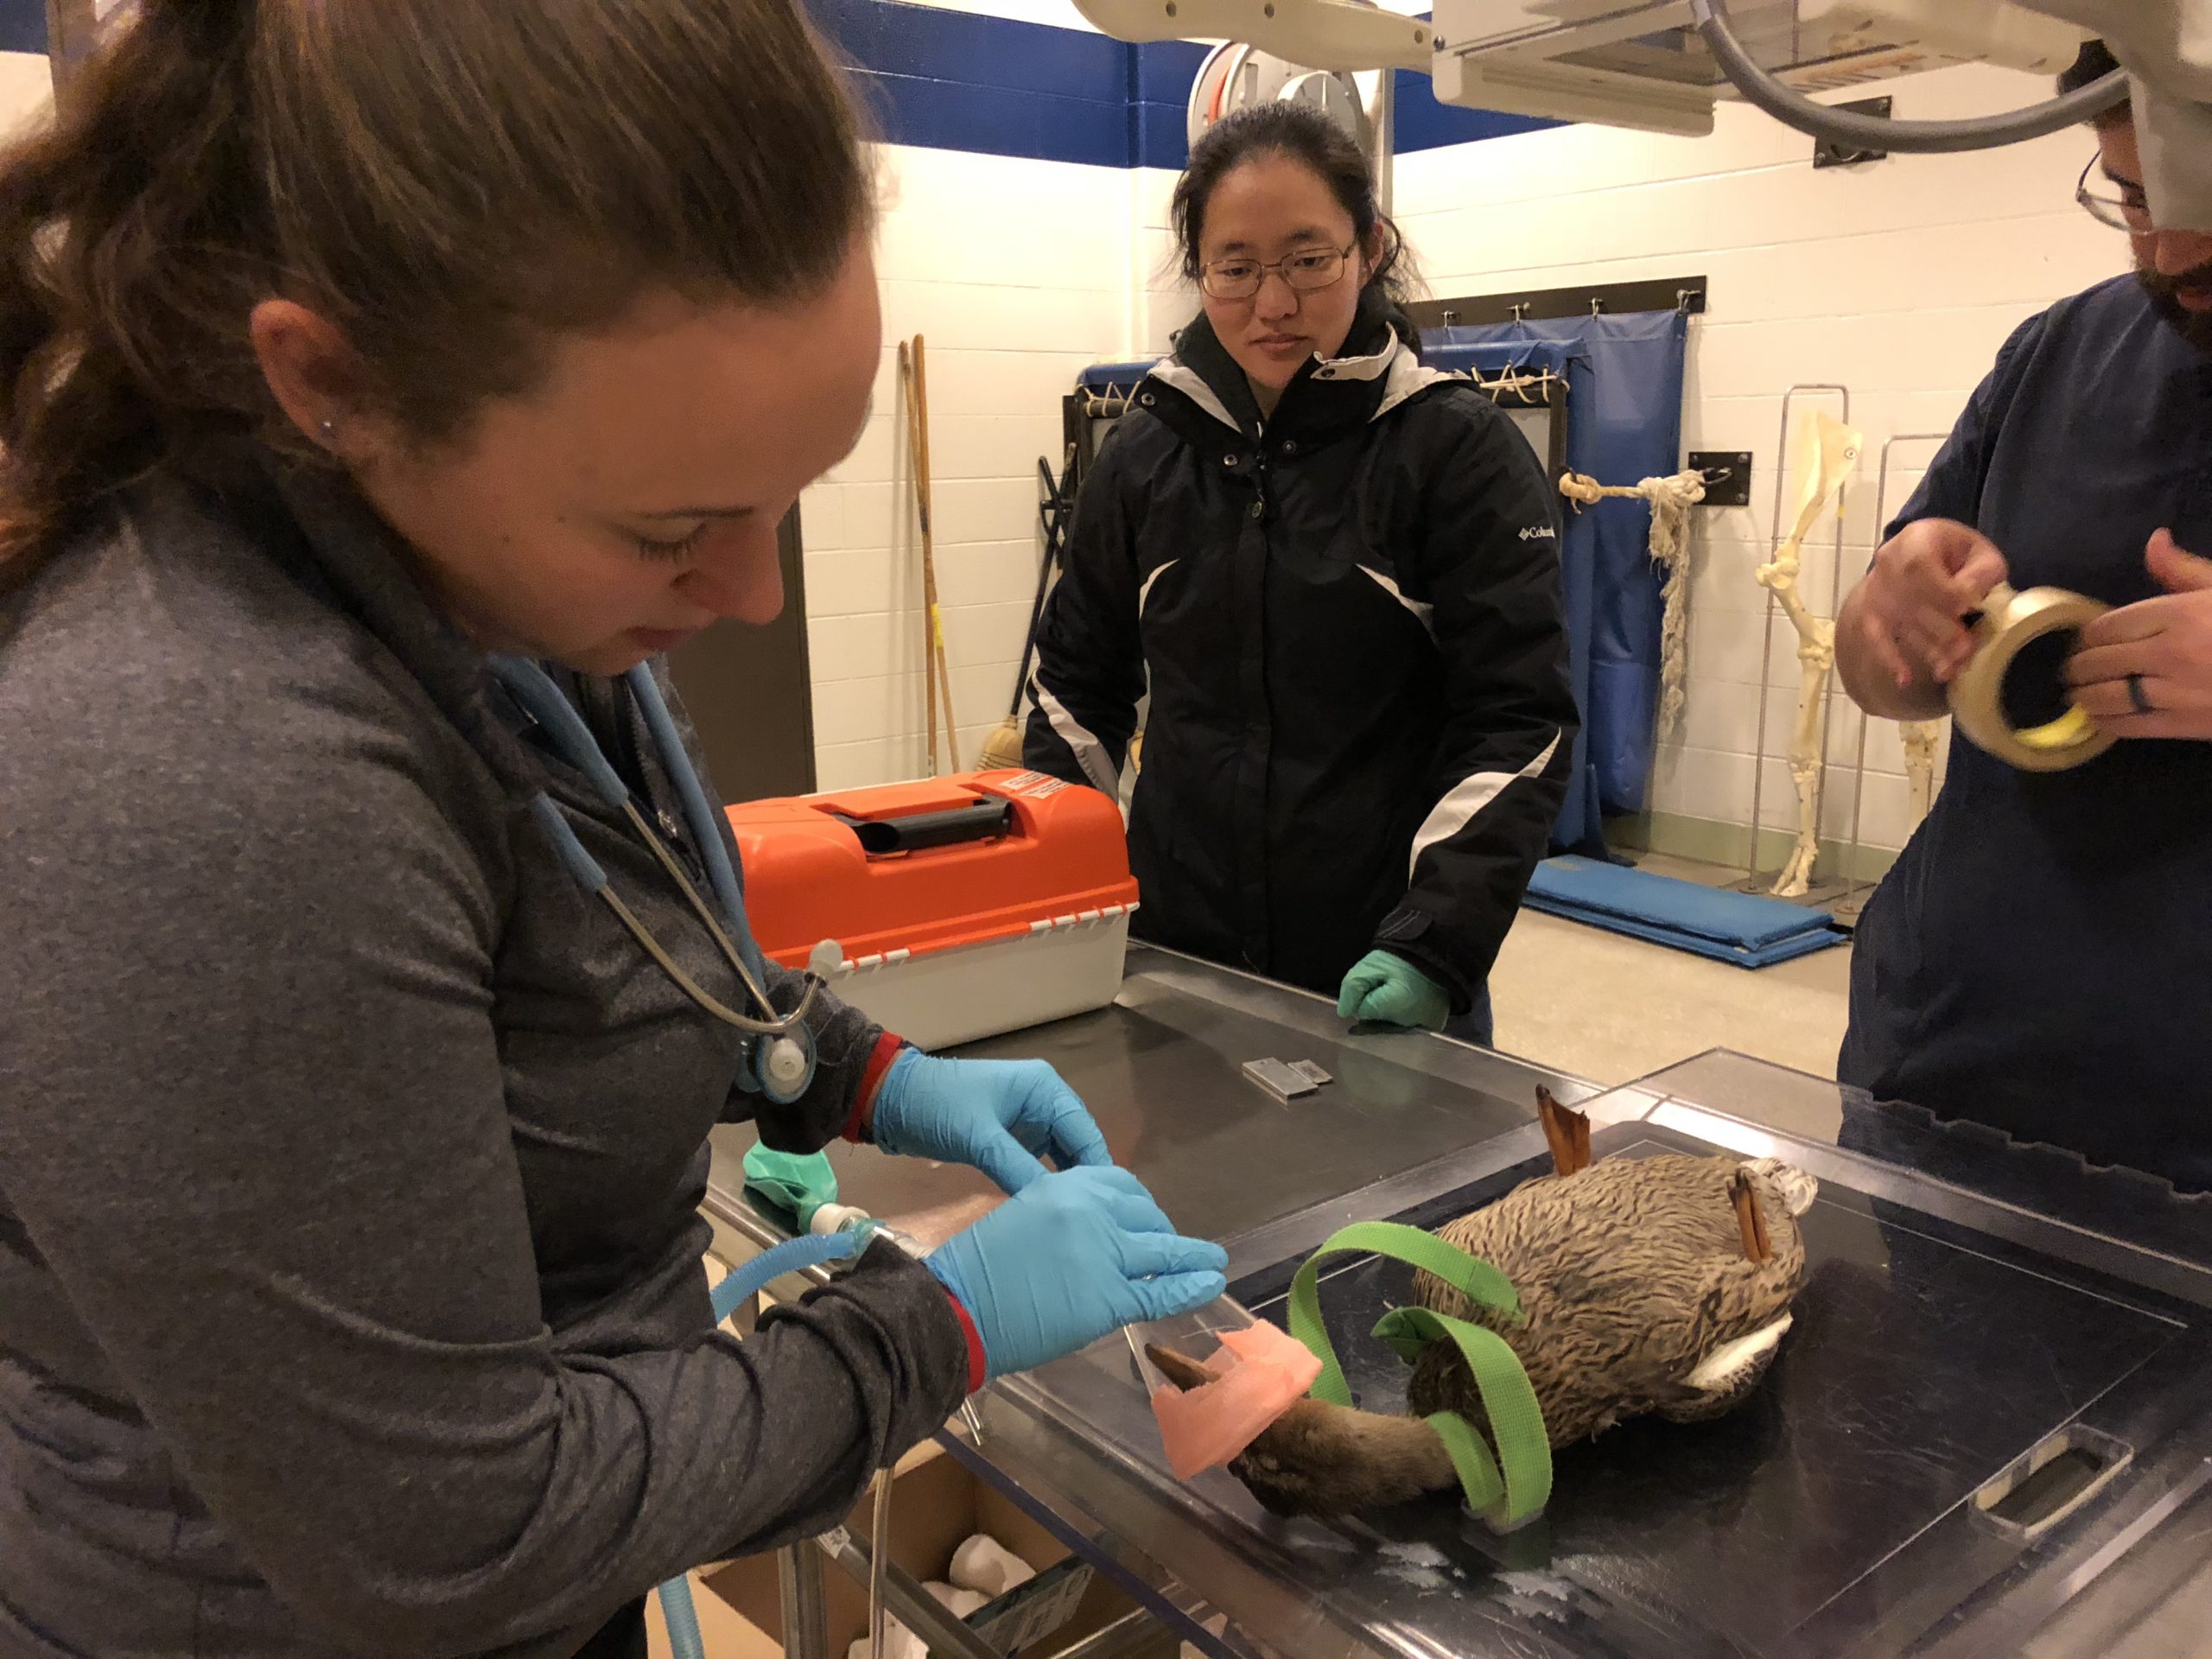

Since the patient was still having trouble walking and there was concern about the lesions on her feet, a plan was made to take radiographs. The patient was sedated and put under anesthesia to take the radiographs, which showed evidence of hind-end trauma. The pelvis appeared to have several fractures but in non-weight bearing portions and therefore was not a cause for concern. There was also an abnormality in the synsacrum, a fusion of the spine and pelvis found in avian species, which could be causing inflammation and spinal problems. However, the issues noted on the radiographs did not seem to be recent, and the plan was to continue treatment with anti-inflammatory medication and provide increased swim time while monitoring for signs of improvement.